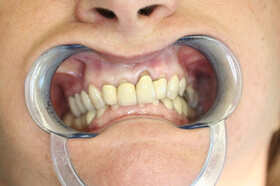

Agresszív fogágybetegség miatt kialakult frontfog elmozdulás – elülső nézet

Agresszív fogágybetegség miatt kialakult frontfog elmozdulás – oldalnézet